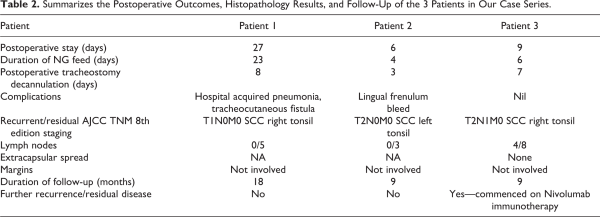

Patient 3 is a 63-year-old woman who was treated with induction chemotherapy followed by radical chemoradiotherapy for a T4N2bM0 tonsillar SCC. 4 months posttreatment a PET CT scan revealed metabolically active lesions within the right tonsil, glossotonsillar sulcus, and several right-sided neck lymph nodes. Patient demographic data is summarized in Table 1 and preoperative imaging is displayed in Figure 1.

Figure 1

Summary of patient preoperative imaging. TOP (Patient 1). Left-axial view contrast enhanced CT showing lesion within right tonsil suggestive of residual disease (red box). Right-axial PET CT showing a strongly FDG avidity within the same tonsillar lesion. MIDDLE (Patient 2). T1 axial view MRI demonstrating a 2-cm mucosal irregularity with increased enhancement in the left tonsillar fossa (red box). BOTTOM (Patient 3). Left-axial view contrast enhanced CT showing malignant appearing changes in right tonsil and glossotonsillar sulcus and an enlarged abnormal right neck node (red box). Right-axial view PET CT showing intense FDG uptake within enlarged right neck lymph nodes. FDG indicates fluorodeoxyglucose; MRI, magnetic resonance imaging; PET-CT, positron emission tomography-computed tomography.